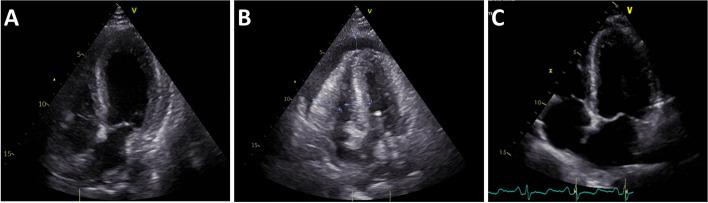

We report the case of an unvaccinated, healthy patient with cardiogenic shock in the context of a COVID-19-associated myocarditis and therapy with simultaneous veno-arterial extracorporeal membrane oxygenation (VA-ECMO) and percutaneous left ventricular decompression therapy with an Impella. The aim of this review is to provide an overview of therapeutic options for patients with COVID-19-associated myocarditis.

The majority of patients required a combination of two assist devices to achieve sufficient cardiac output until recovery of left ventricular ejection fraction. Due to the rapid onset of this fulminant cardiogenic shock immediate invasive bridging therapy in a specialized center was lifesaving.